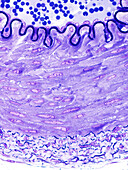

13742427 - Elastic artery, light micrograph

13742425 - Elastic arteries, light micrograph

13742428 - Elastic artery, light micrograph

13218770 - Elastic artery, light micrograph

12360856 - Wall of an elastic artery, light micrograph

12360848 - Wall of an elastic artery, light micrograph

12360853 - Elastic artery, light micrograph

12960253 - Blood vessels,light micrograph